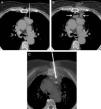

We report the case of a 73-year-old woman with no significant clinical history, in whom an anterior mediastinal mass was detected incidentally. Image-guided core needle biopsy (CNB) of the mass was performed, but the theoretical trajectory of the biopsy needle was interrupted by the pulmonary parenchyma of the left upper lobe between the anterior chest wall and the mediastinal mass (Fig. 1A). To avoid puncturing the pleural surface and the pulmonary parenchyma with the biopsy needle, we used an intramuscular needle to instill 100ml saline into the scant fatty tissue of the patient's anterior mediastinum, thus creating a collection of fluid (Fig. 1B), which provided a safe approach route, avoiding perforation of either the pleura or the left lung. The biopsy needle was then inserted between the left internal mammary vessels and the left lateral edge of the sternum, traversing the previously created fluid collection (Fig. 1C). Histological material was collected that confirmed the diagnosis of thymoma, World Health Organization classification type A. Cytological diagnosis of thymomas using fine needle aspiration can be difficult to interpret, so histological material retrieved by CNB is preferable, although this technique is often accompanied by a higher rate of complications (pneumothorax, lung bleeds).1,2 Hydrodissection with saline is a simple technique that creates a safe access route for the histologic diagnosis of anterior mediastinal masses.

(A) Axial chest CT image showing an anterior mediastinal mass (asterisk). The white line indicates the theoretical path of the biopsy from the anterior chest wall to the mediastinal mass, traversing the pleural surface and the left pulmonary parenchyma. (B) Axial chest CT image showing the creation of a small fluid collection (arrows) between the anterior chest wall and the mediastinal mass. (C) Axial maximum intensity projection CT image of chest showing the biopsy needle crossing the fluid collection (L) and penetrating the mediastinal mass (M).